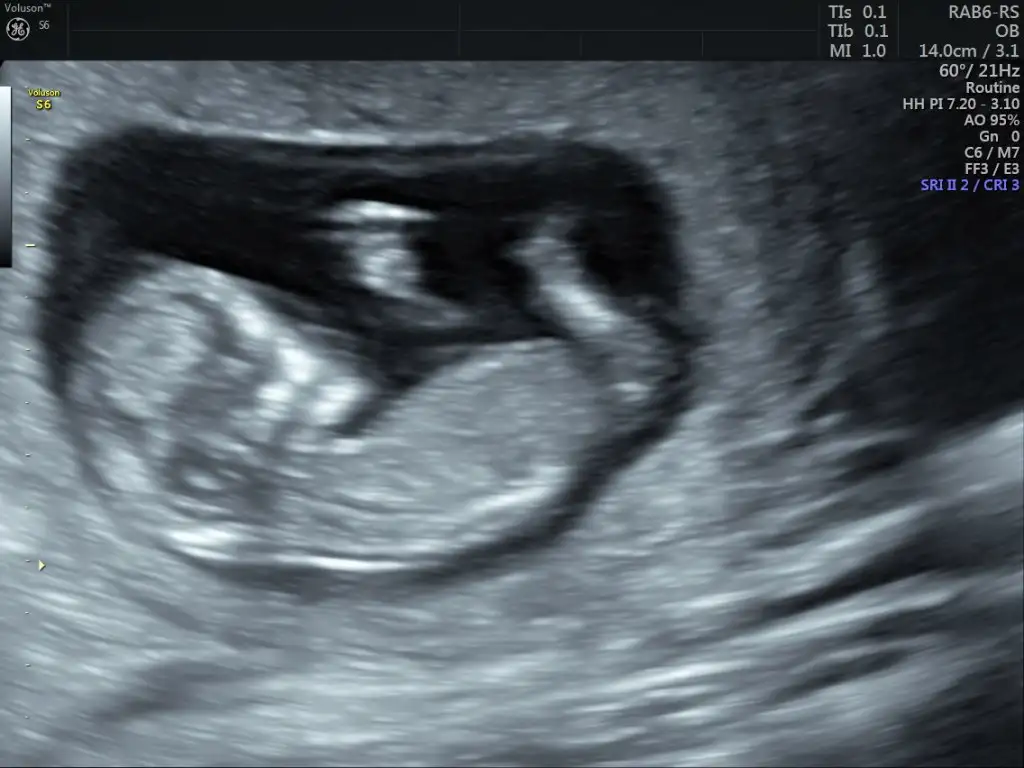

Canım erkek gibiBenimkinede bakarmısınız 12+2 haftalık ben kız olduğunu düşünüyorum ama bilemedim

Bir çıkıntı var ama anlayamadım görüntünüz aslında çok net.Benimkinede bakarmısınız 12+2 haftalık ben kız olduğunu düşünüyorum ama bilemedim